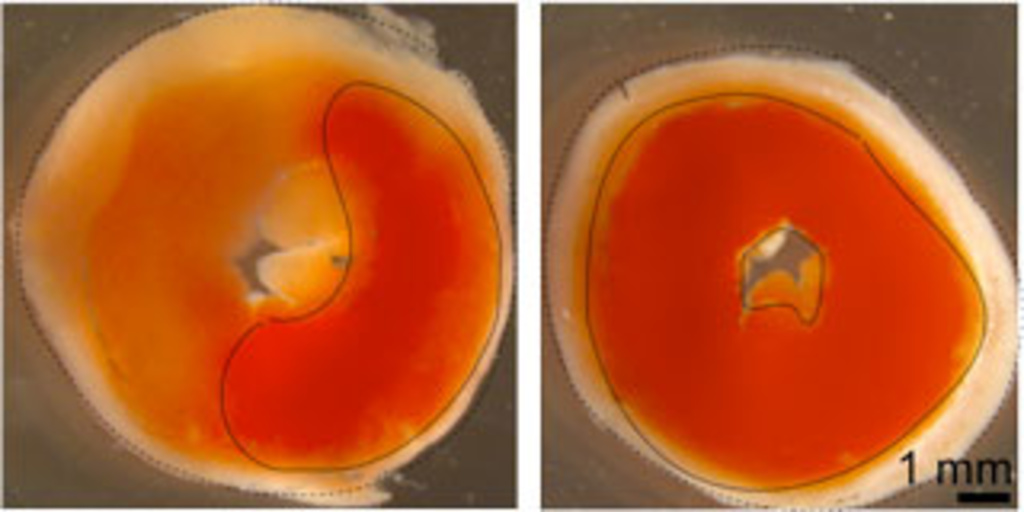

Enzyme Triggers Heart Failure Iowa Now The University Of Iowa